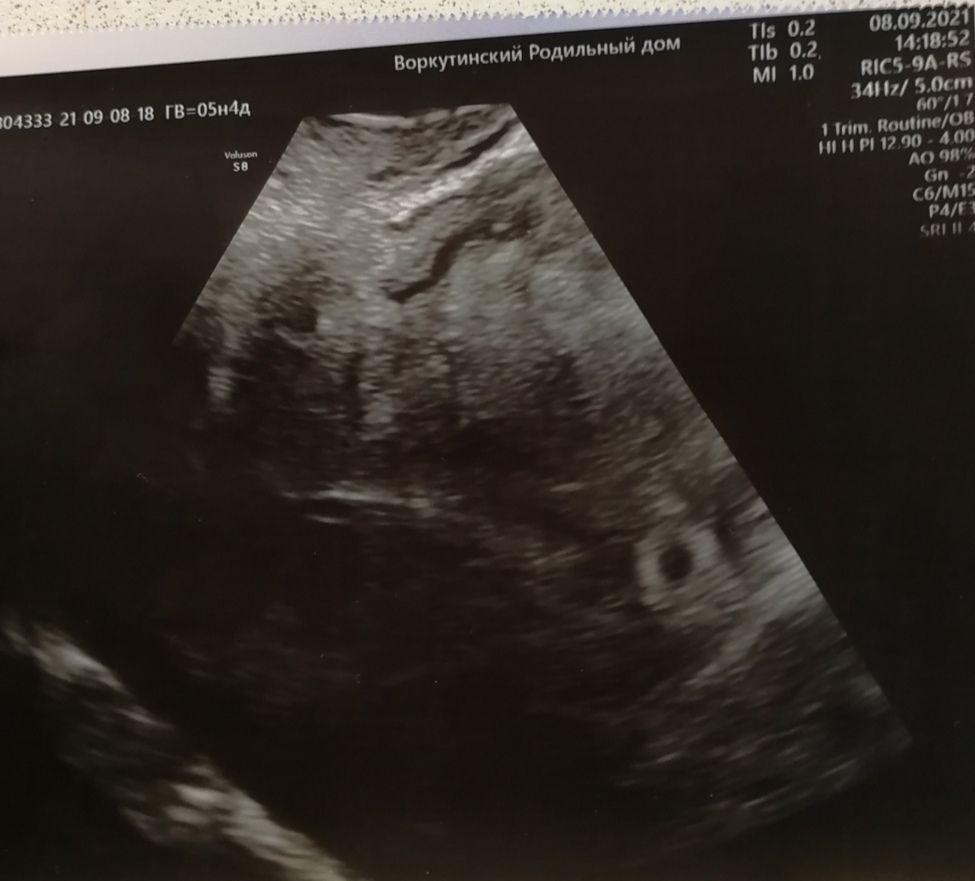

увидела только ПЯ 13,5 мм и все

но мне кажется я что-то вижу!!! Поддержку не отменила, буду ждать!!! Записалась завтра на экспертное узи! Посмотрите, видите что-нибудь?

На фото пусто, шанс мал, так как нет даже желточного мешочка☹️ Хотя он раньше эмбриона появляется, а потом на «колечке» появляется «бриллиант»- эмбрион. Не хочу расстраивать, но вряд ли что-то появится

Во первых "срочно" на МА точно не нужно. Если это первое УЗИ, обязательно переделать через неделю (а лучше сейчас проверить у другого узиста и динамику смотреть у него же потом). По фото действительно пусто сейчас. То что вы обвели на фото в комментариях это уже за пределами ПЯ. Но анэмбриония ставится при размерах ПЯ 20-25 мм, так что у вас шансы ещё есть, что все появится, чего вам и желаю 🙌